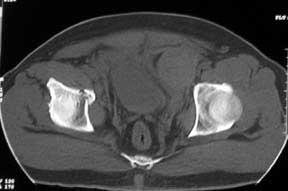

Middle aged male who was injured when a log of wood fell on him ina saw mill. Haemodynamically patient stable. No visceral injuries detected. The following musculoskeletal injuries detected: 1) Closed fracture femur. 2) Pubic symphysis disruption. 3) Right inf pubic rami fracture. 4) Right acetabular fracture. Head of femur located. 5) Right Sacroiliac joint anterior opening.

Your plan sounds fine. The acetabular fracture looks like a high ramus fracture that happens to enter the acetabulum. The CT scan is blurry, and you haven't provided any oblique views of the acetabulum - but my guess is that the 'tab is concentric.

Here are the post op pictures.